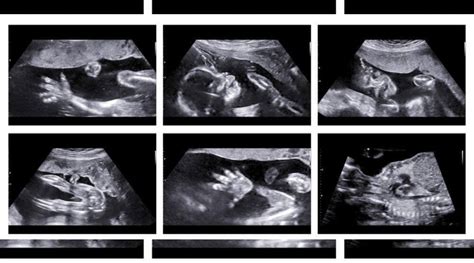

Now, the 20-week scan, also known as the anatomy scan, is a big deal. It’s when your doctor gets a good look at your baby’s development, checking everything from the brain to the toes. This is where the term iiioschowsc common might get thrown around, and it’s essential to understand what it refers to in the context of this scan. We’re going to break down what it could mean, possible outcomes, and how it relates to your pregnancy. Buckle up; let’s get into it.

Alright, let’s get down to the nitty-gritty. So, what exactly is iiioschowsc common ? In the context of a 20-week scan, it’s a term or phrase that, while not a recognized medical acronym, might signal the possibility of a particular condition or observation made during the ultrasound. I am not able to give a definition for this term. The scan itself is a detailed ultrasound used to examine the baby’s organs, and measure development. The scan checks for things like the baby’s heart, brain, spine, kidneys, and limbs. It also checks the placenta and the amount of amniotic fluid. This scan is your chance to get the first real peek at your baby, so it’s a super exciting time!

What makes the 20-week scan so significant is that it allows medical professionals to identify potential health problems early on, in some cases allowing for interventions during pregnancy or immediately after birth. This is not the only scan during pregnancy, but it’s one of the most comprehensive and informative.